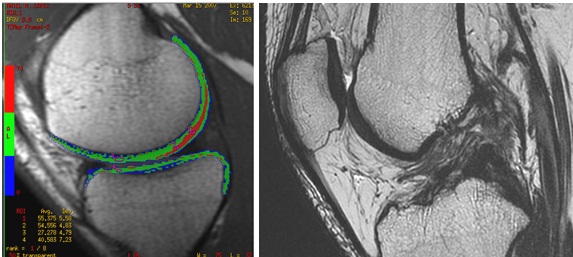

Rodilla

En rodilla es muy raro la necesidad de realizar Artroresonancia, algunos médicos ortopedistas han solicitado este estudio en casos de un meniscos post operados en donde no haya quedado claro de acuerdo al tiempo de evolución si hay tejido de granulación o ruptura.

Secuencia Cartigram, T2 FSE rotura del ligamento cruzado anterior